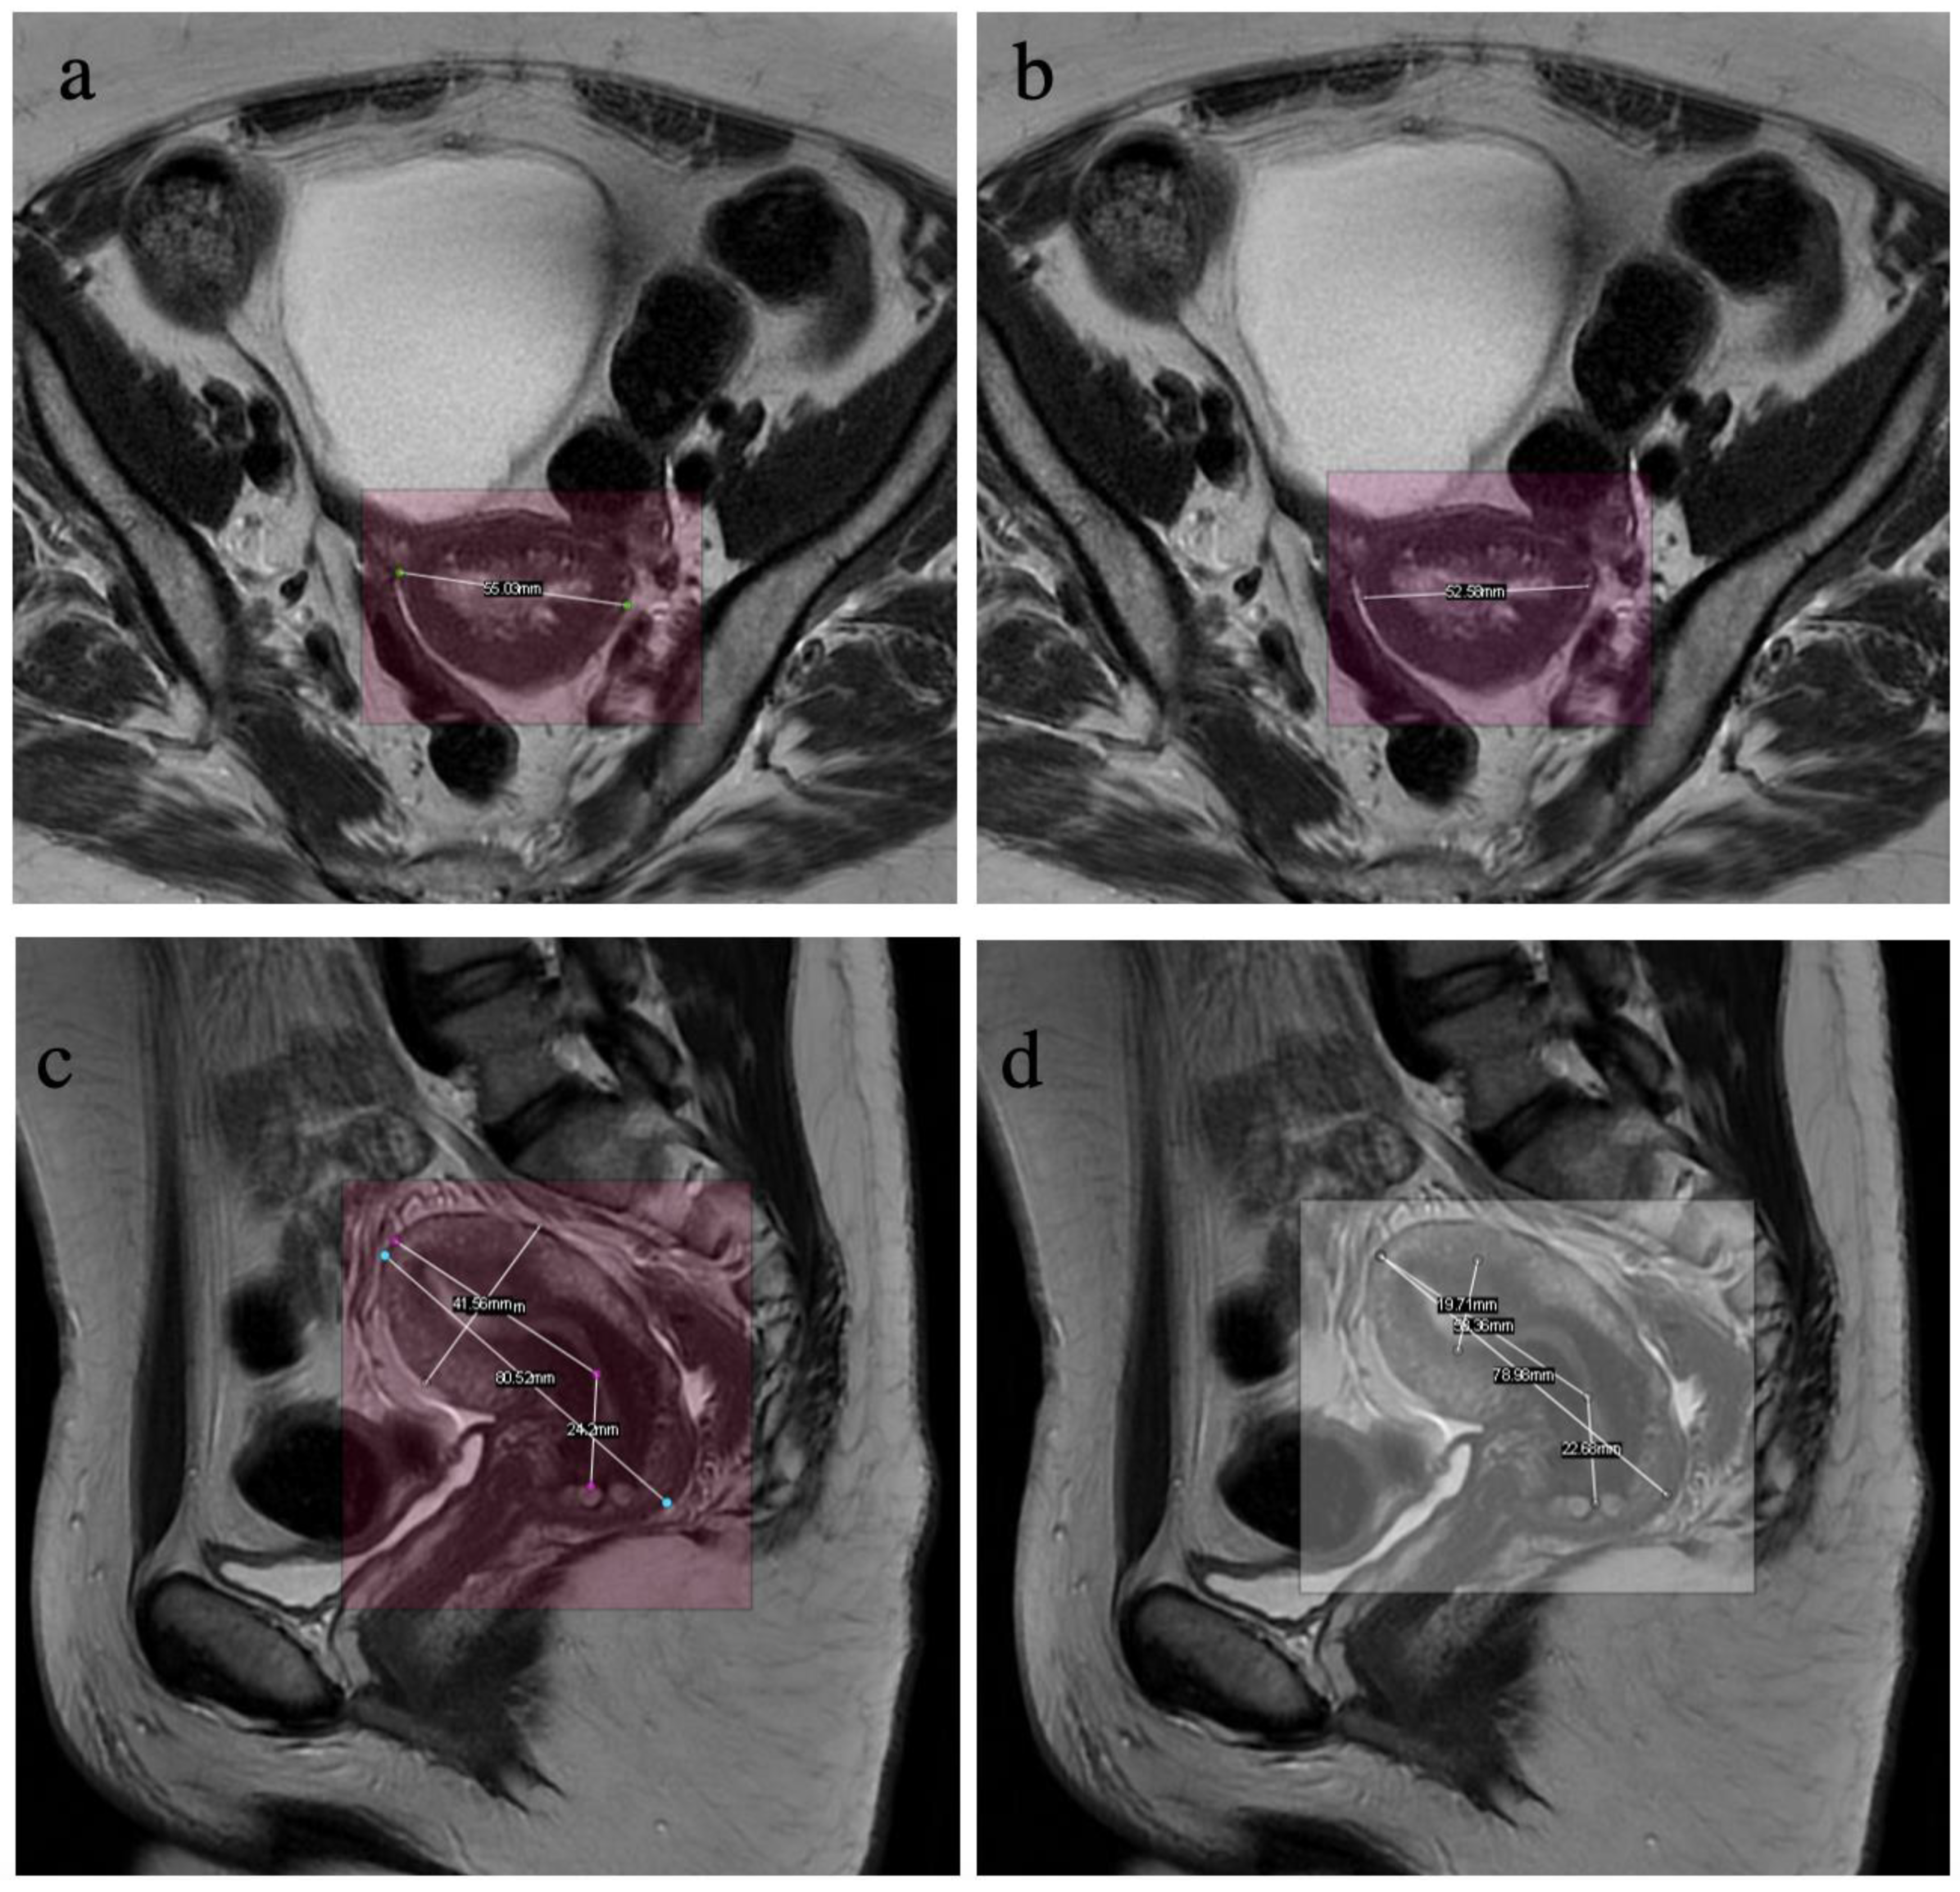

| Width | 32.16 | 35.95 | 93.65 | 90.98 | 52.72 | 52.58 | 54.42 | 54.60 | 12.35 | 11.06 |